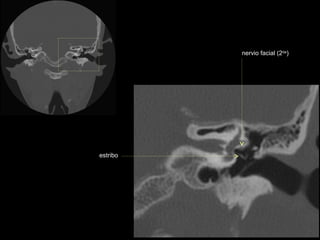

CATEDRA DE RADIOLOGIA U.N.L.P.   Hueso temporal normal        Edición 2002

estribo (cruras)

nervio facial

ventana oval

martillo

yunque

cóclea

vestíbulo

conducto semicircular externo

nervio facial (2da)

estribo